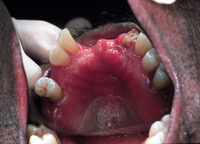

Candidíase oral

Candidíase pseudomembranosa no vírus da imunodeficiência humana (HIV)

Do acervo de Fariba Younai, UCLA School of Dentistry, Los Angeles